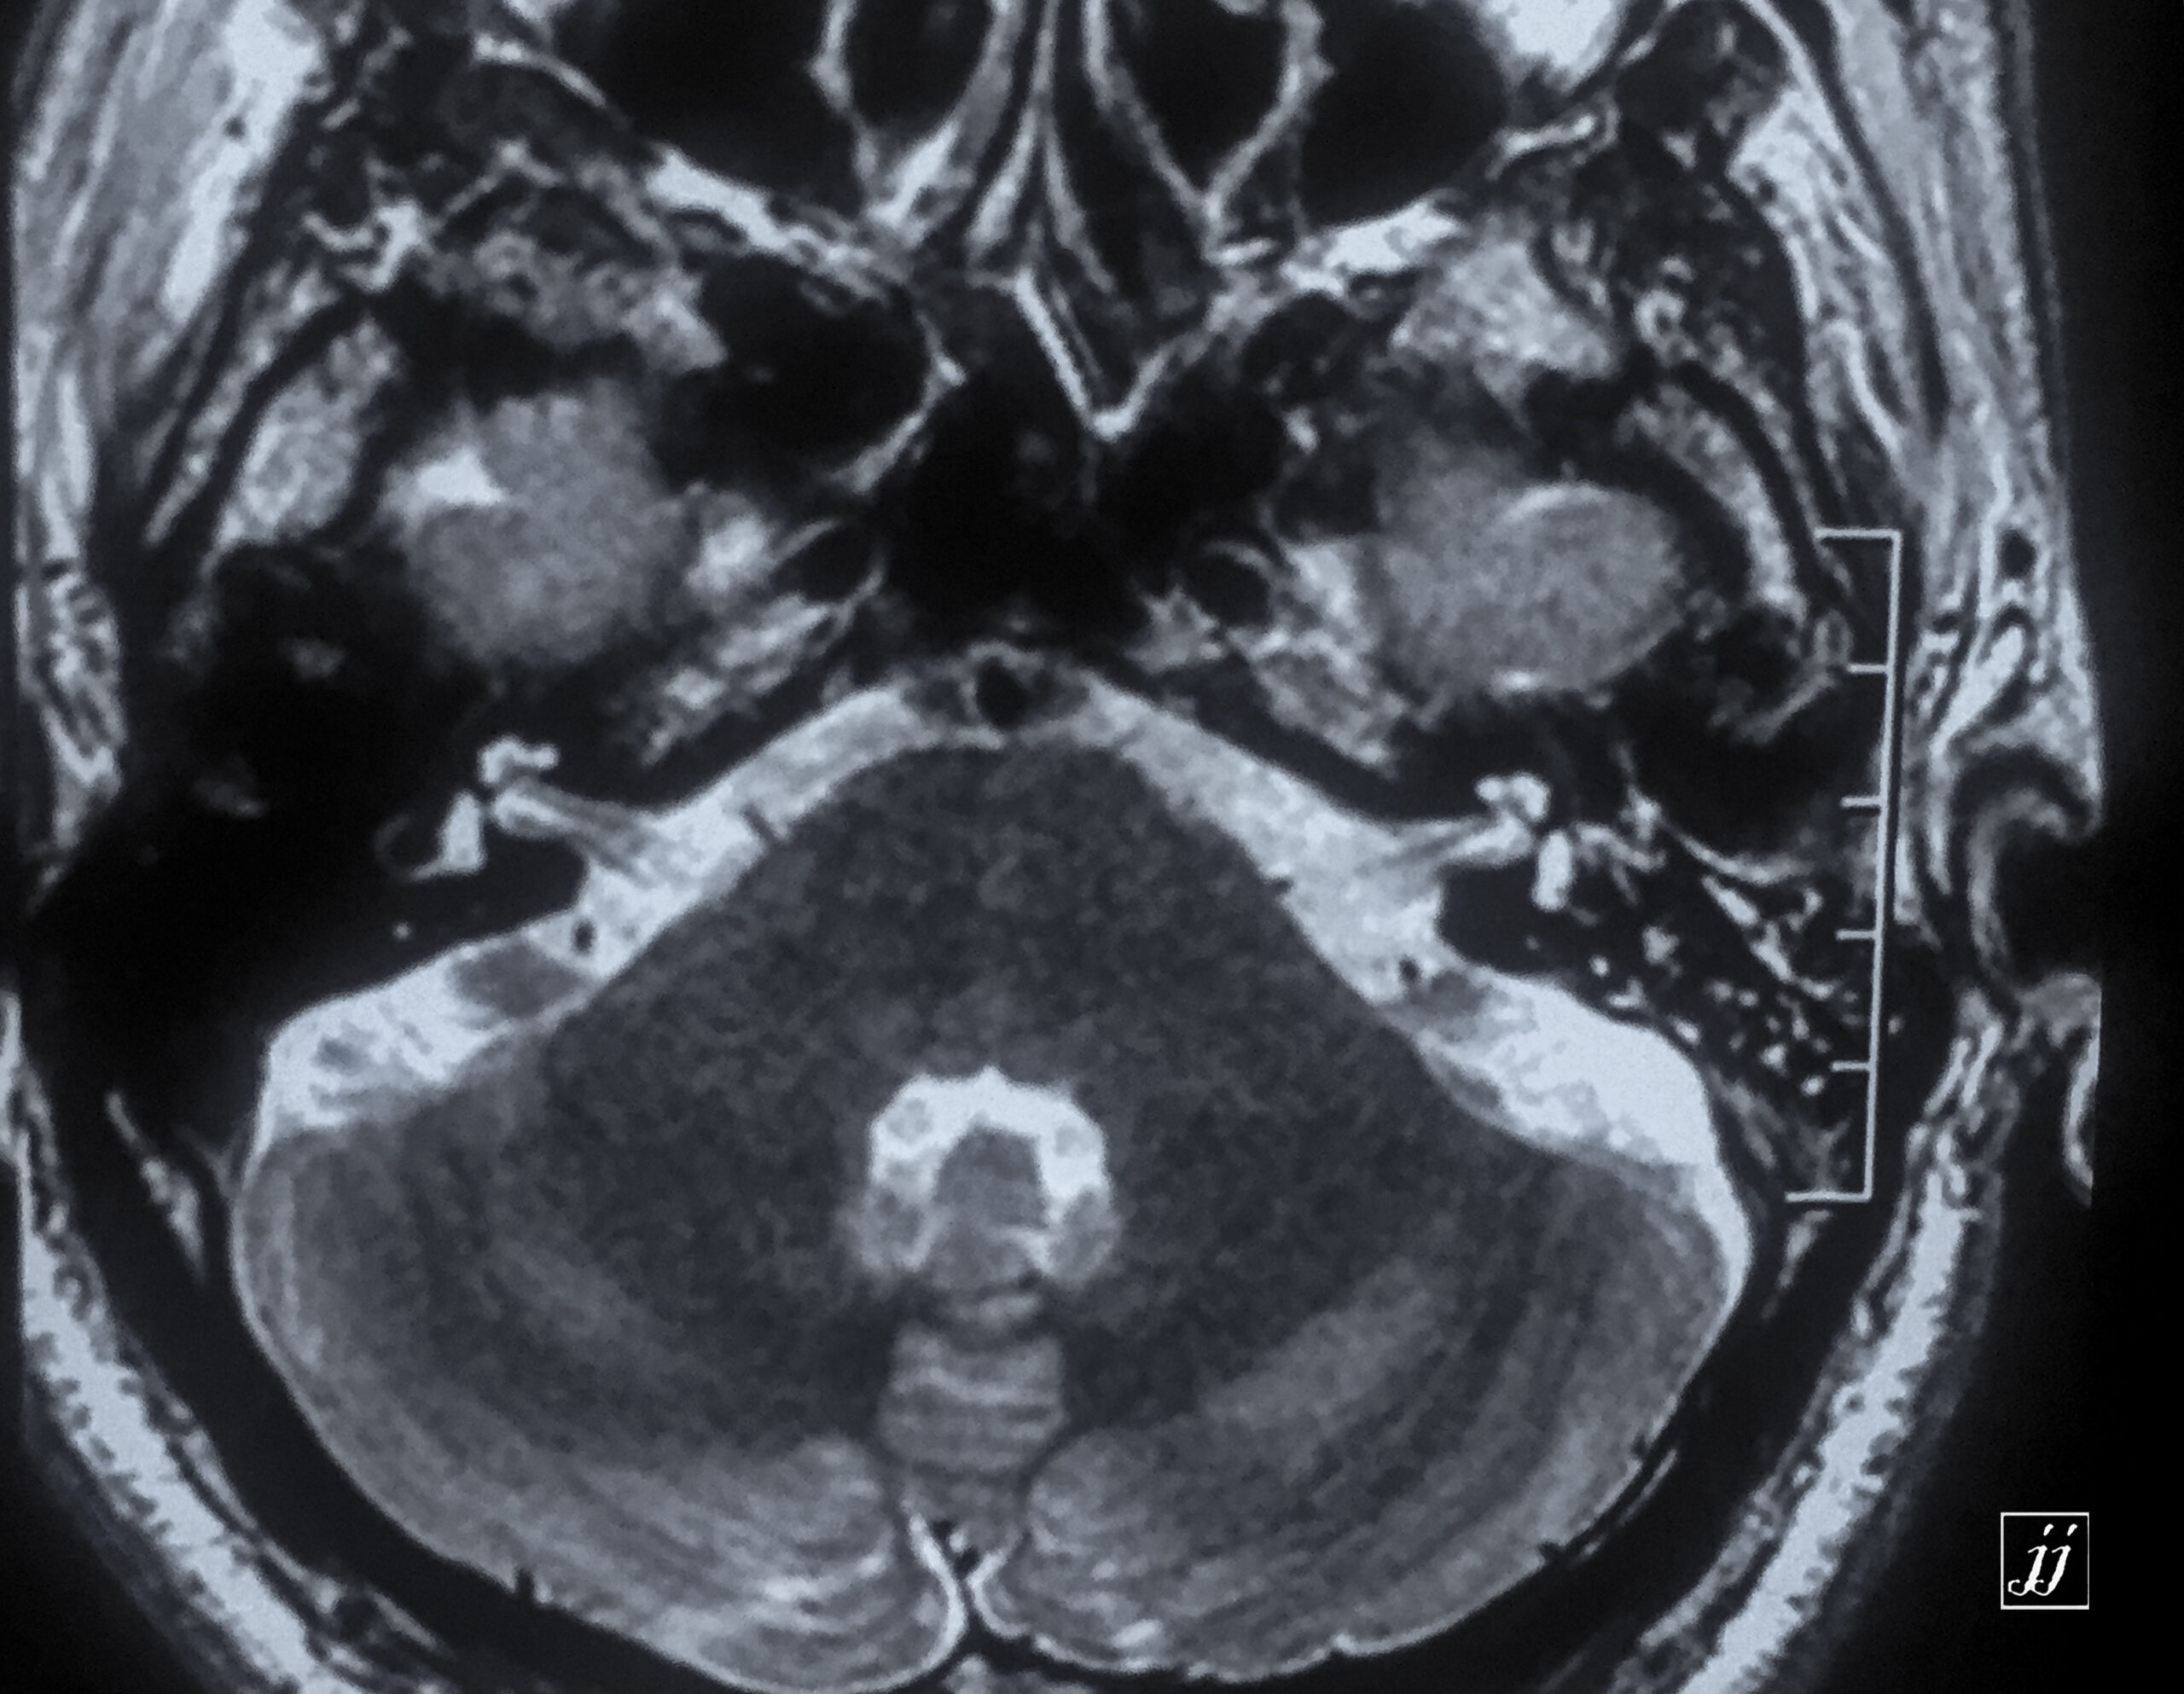

Brain- left side COM (3)